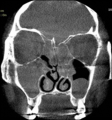

코 질환의 여러증상 중에서도 코막힘은 특히 환자를 가장 불편하게 한다. 이런 코막힘의 흔한 원인중 하나가 비중격만곡증이다. 비중격은 양쪽 콧구멍을 나누는 칸막이 뼈로, 이것이 어느 한쪽으로 휘어져 있는 경우를 비중격만곡증이라 한다.